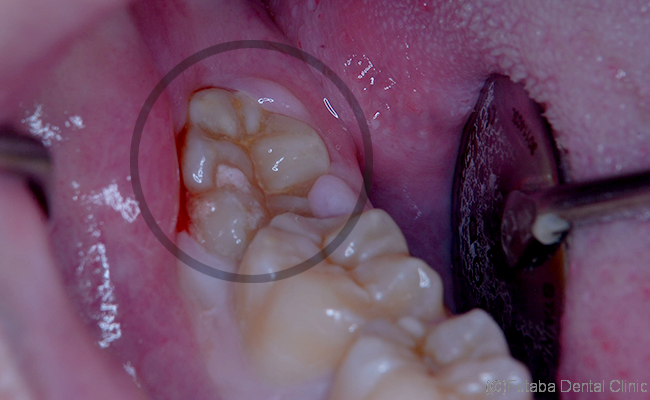

今回は、頭は出ているが、萌出するスペースがない為

手前に倒れた状態で、生えています。

この状態ですと、手前の歯との間に汚れが溜まりやすく、

虫歯を作ってしまう可能性が高くなってしまいます。

また、歯周病にもなりやすい状況です。

しかも、手前の歯に接触している為

手前の歯を前方へ押してしまい、

前歯の歯並びが乱れる原因の一つになってしまいます。